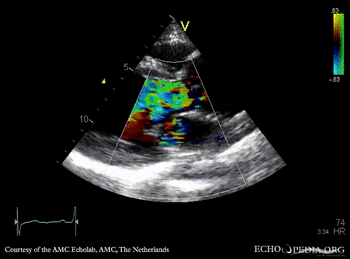

E00446.gif E00447.gif

A5CH A5CH: Color Doppler, severe aortic regurgitation